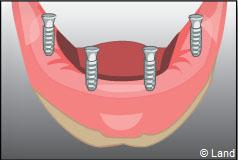

Exemple d’une réhabilitation complète implantaire

– le remplacement de plusieurs dents manquantes par un bridge sur implants. Cela évite l’appareil amovible.

Deux techniques sont possibles. Elles font appel à la barre de rétention ou aux boutons-pressions.